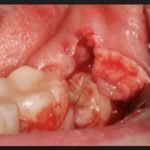

- Бывает, что лезет зуб мудрости горизонтально – что делать в этом случае, специалист решает по ситуации. Чаще всего его по частям распиливают при помощи бормашины.

Процесс длится 10-40 минут в зависимости от того, насколько сложно располагается «восьмерка». Все манипуляции проходят под местным обезболиванием. Однако подобные операции противопоказаны беременным женщинам из-за высокой вероятности заражения раны и осложнений. Также стресс, испытанный матерью, отразится на ребенке, даже вызвав преждевременные роды. Поэтому если у беременной лезет зуб мудрости, опухла щека, появились характерные симптомы прорезывания, их блокируют мягкими препаратами либо просто ждут, когда процесс роста завершится.